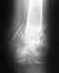

Все, что представлено - фото заключения с описанием вывиха. Вряд ли можно "оценить результаты операции", если нет никакой информации о том, какая это была операция, что и как сделали, какая рентгенологическая картина после нее.